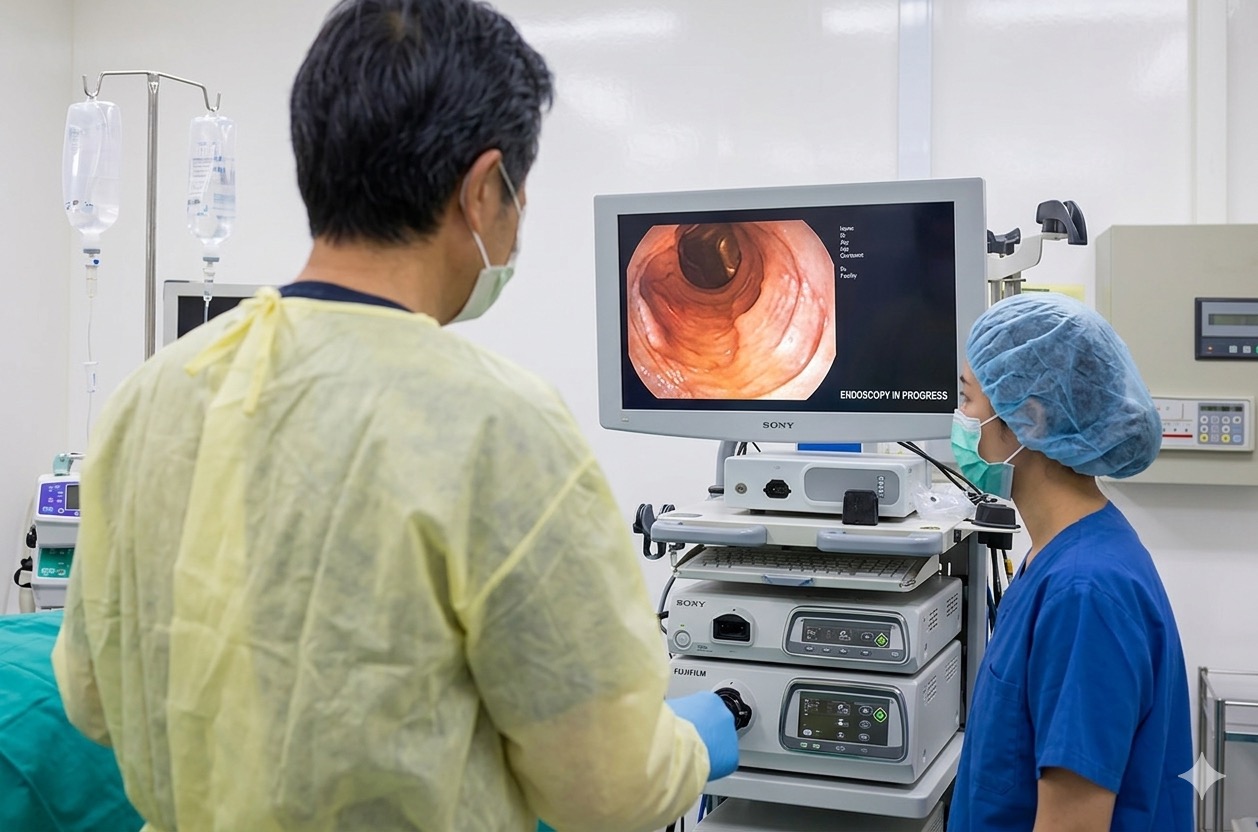

全ての内視鏡検査を経験豊富な消化器内視鏡専門医が実施。確かな技術で安心・安全な検査をご提供いたします。

ご希望の方には鎮静剤を使用し、眠っている間に検査が終了。不安や苦痛なく受けていただけます。

オリンパス最新内視鏡システムEVIS X1を導入。高精細画像で微小な病変も見逃しません。

食道・胃・十二指腸を直接観察する検査です。経鼻内視鏡にも対応しており、患者様のご希望に合わせて検査方法をお選びいただけます。鎮静剤を使用することで、眠っている間に検査を受けることも可能です。ピロリ菌検査や組織検査(生検)も同時に行えます。

大腸全体を直接観察し、ポリープや炎症、がんなどの病変を発見する検査です。検査中に発見されたポリープはその場で切除が可能です(日帰り手術)。鎮静剤を使用し、苦痛の少ない検査を心がけています。

経験豊富な専門医が丁寧に検査を行います。鎮静剤をご使用の方は、眠っている間に検査が終了します。検査中に必要に応じて組織検査(生検)を行う場合があります。

検査終了後、撮影した画像をお見せしながら結果をわかりやすくご説明いたします。鎮静剤を使用された方は、院内のリカバリールームで30分〜1時間ほどお休みいただいた後にご説明します。病理検査の結果は約1週間後となります。